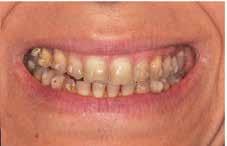

A felnőtt páciensek kezelése során általában egyszerre több ellátásra szoruló elváltozást is diagnosztizálhatunk: hiányzó fogak, kopott fogazat, esetleg régi, nem megfelelő, sérült fogpótlások, rendellenes helyzetben lévő fogak stb… Ezen páciensek kezelésekkel kapcsolatos kérései mindig az esztétikai vagy a rágással kapcsolatos kívánságaik kielégítését szolgálja. A kezelések során a fogorvosoknak nem csak a páciensek kéréseinek teljesítésére, hanem ezzel egyidejűleg a fogazat általános megjelenésének és funkciójának lehetőség szerinti javítására is törekedniük kell. Mindemellett a lehető legtöbb saját foganyag megőrzését és az évek során elvesztett kemény- és lágyrészek pótlását (pl.: hiányzó fogak, sorvadt állcsontgerinc, lágyszöveti defektusok) is szem előtt kell tartaniuk, úgy, hogy közben egy hosszú távon fenntartható eredményekkel járó kezelési tervet állítanak össze. Ezek mindig összetett esetek. Annak érdekében, hogy a fentiekben megfogalmazott összes kezelési célt teljesíteni tudjuk, interdiszciplináris megközelítésre van szükség. Az ilyen komplex rehabilitációs kezeléseket „fogászati megfiatalításnak” nevezzük. Ezeknek a beavatkozásoknak lényege az elhasználódott fogazat biológiai szempontokat figyelembe vevő minimál invazív módon történő helyreállításában rejlik, mely folyamat végére a páciensek fogai visszanyerhetik fiatalkori megjelenésüket.

A rehabilitációs kezeléseknek a célja, hogy a páciensek a lehető leghosszabb időn keresztül képesek legyenek mosolyogni és rágni. A protetikai kezeléseket végző fogorvosoknak helyre kell tudni állítaniuk a fogívek szabályos lefutását és az alsó és felső fogív között megfelelő interokkluzális érintkezéseket kell létrehozniuk. Így lehet csak az ellátás befejezését követően elért végeredmény biológiai szempontokat figyelembe vevő esztétikáját, funkcionális megfelelőségét, hosszú távú fenntarthatóságát biztosítani.

Nagyon fontos, hogy már a kezelések elején meghatározzuk, hogy melyek azok a hiányzó fogak, amelyeket a későbbiekben pótolni szeretnénk, valamint helyesen diagnosztizáljuk a kariológiai, endodonciai vagy parodontológiai okok miatt ellátást igénylő elváltozásokat. Szintén kiemelt jelentőséggel bír a fogak megtarthatóságának kiértékelése. A kezelési terv felállítása során tisztában kell lennünk azzal, hogy mely fogak alkalmasak fogpótlások ideiglenes vagy végleges elhorgonyzására.

A preprotetikai fázisban el kell látnunk a diagnosztizálásra került kórfolyamatokat, megfelelő pozícióba kell állítanunk a megtartani kívánt fogakat, pótolnunk kell az elvesztett csontállományt, valamint gondoskodnunk kell az íny megfelelő állapotáról. Ha szükség van rá, úgy a foghiányok pótlására szolgáló dentális implantátumok is ebben a fázisban kerülnek behelyezésre. Általánosságban elmondható, hogy azokat a kezeléseket, amelyek befejezése biológiai okok miatt hosszú időt vesz igénybe (pl.: fogszabályozás, csontpótlás, implantáció), a lehető leghamarabb érdemes elkezdeni.